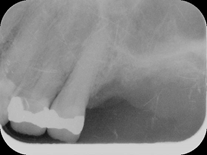

Depois de curetado os alvélos, foram preenchidos com material aloplástico: Gengimix + Adesivo cirúrgico. Para manutenção do material enxertado a ferida cirúrgica foi recoberta com uma membrana de colágeno reabisorvível. Neste procedimento é importante o material ser bem comprimido e protegido, não haverá sangramento após a intervenção. p22p21Importante notar que as raízes do primeiro molar foram seccionadas, para a nutenção do alvéolo remanescente, o segundo molar não houve necessidade deste procedimento. Depois de colocada a membrana tudo foi muito bem suturado, e colocado cimento cirúrgico. p23p24Estas são as duas radiografias a primeira, logo após a cirurgia e curetagem dos alvélos, (ela está invertida, para comparação). A segundo é após o preenchimento dos alvélos com material de ROG.